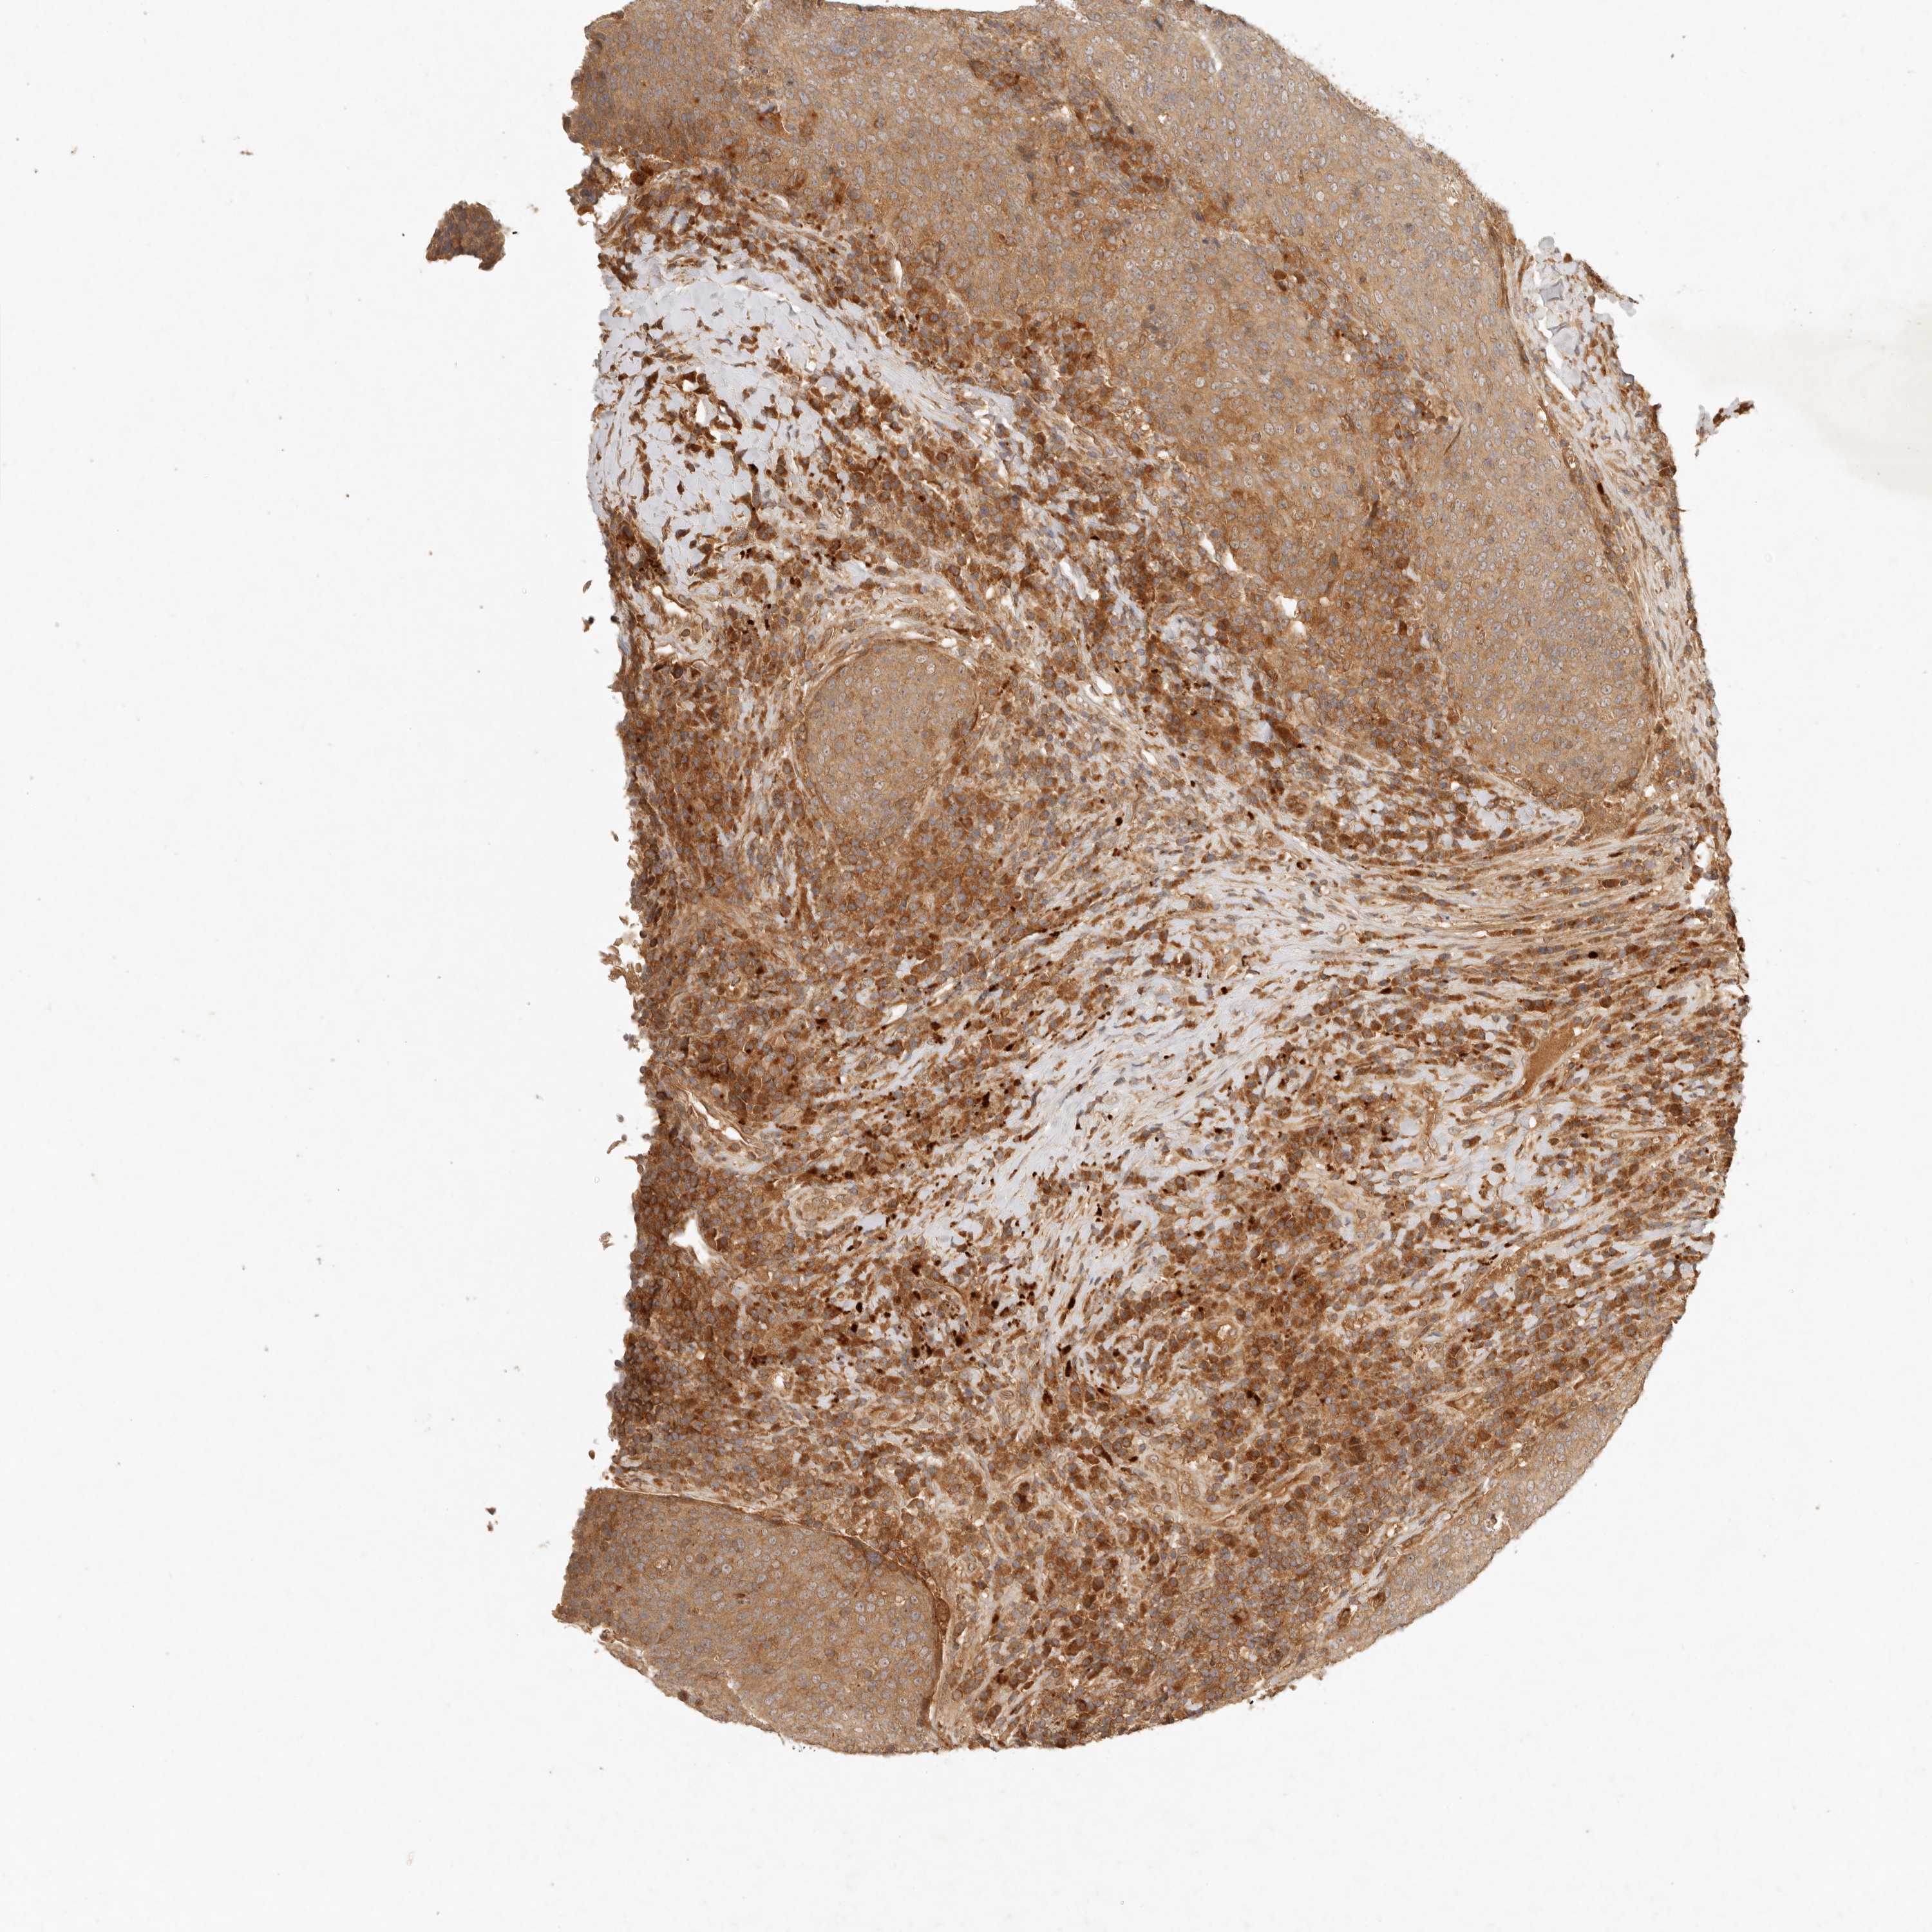

HEAD AND NECK CANCER - Protein expressioni

A mouse-over function shows sample information and annotation data. Click on an image to view it in a full screen mode. Samples can be filtered based on level of antibody staining by selecting one or several of the following categories: high, medium, low and not detected. The assay and annotation is described here.

Antibody stainingi

Antibody staining in the annotated cell types in the current human tissue is reported as not detected, low, medium, or high, based on conventional immunohistochemistry profiling in selected tissues. This score is based on the combination of the staining intensity and fraction of stained cells.

Each image is clickable and will lead to virtual microscopy that enables deeper exploration of all samples and also displays staining intensity scores, fraction scores and subcellular localization as well as patient and tissue information for each sample.

Antibody HPA029511

Staining

High

Medium

Low

Not detected

Intensity

Strong

Moderate

Weak

Negative

Quantity

>75%

75%-25%

<25%

None

Location

Nuclear

Cytoplasmic/membranous

Cytoplasmic/membranous,nuclear

Squamous cell carcinoma, NOS

Squamous cell carcinoma, metastatic, NOS

Adenocarcinoma, NOS